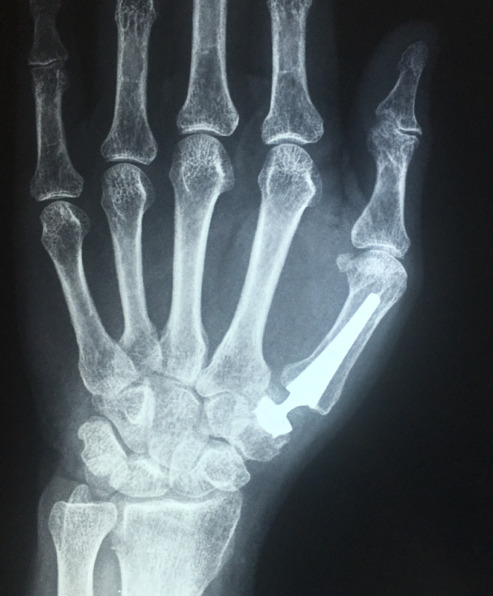

“Como siempre a la vanguardia de la ortopedia especializada en el país, hoy 7 de Abril del 2015 el Dr. Fidel Cayón se convirtió en pionero en el país en colocar una prótesis trapeciometacarpiana.

Esta prótesis busca aliviar el severo dolor de la base del pulgar que se produce por el desgaste articular de la misma (artrosis). Al momento, en el país son muchos los pacientes que presentan un cuadro intensamente doloroso de esta zona que permite la movilidad adecuada del dedo mas importante de la mano, dolor que incluso llega a impedirles la escritura.

Esta prótesis se presenta como una gran posibilidad de recuperación de movilidad y alivio lo que permite a nuestros pacientes recuperar la funcionalidad del dedo mas importante de su mano.

Comparto las fotos de la paciente, tanto las que fueron tomadas en aquella época como las actuales, en que podemos ver la movilidad que ha alcanzado y como esta le ha permitido mantenerse en sus actividades habituales sin dolor.